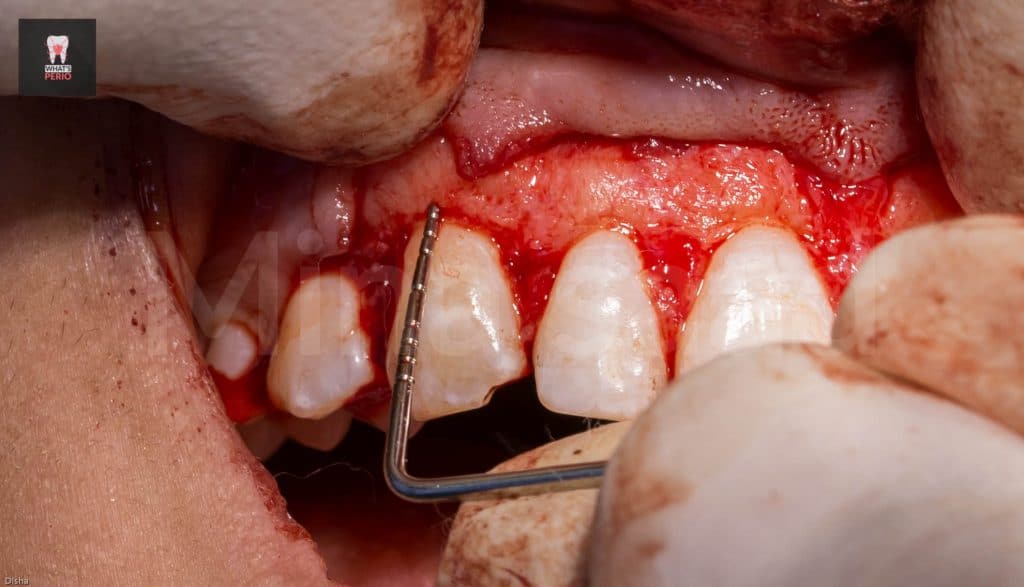

-The guide was placed again over labial plate of bone & it was noted that its apical level is higher than alveolar crest level.” Which confirms that the design on CBCT was accurate”

-Ostectomy was made using a rose head diamond stone then the guide was put in place again & it was observed that the apical level & the alveolar crest is at the same level now.

-A periodontal probe was placed between CEJ & alveolar crest to measure the distance which was 2mm. “ensuring that the digital guide is accurate”